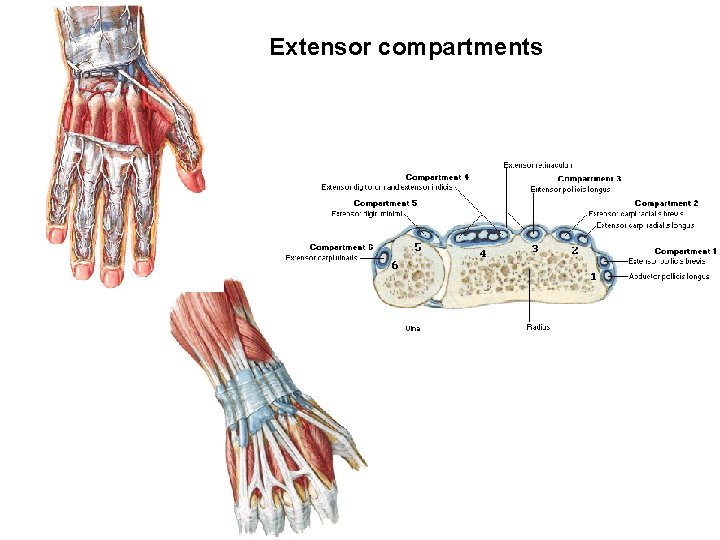

Extensor compartments